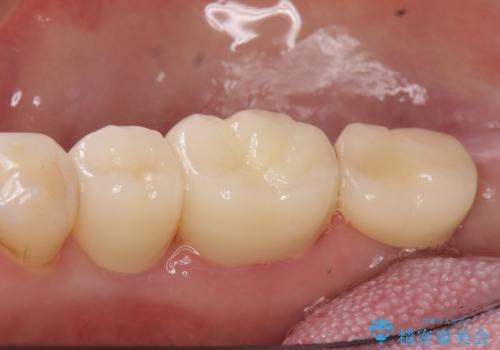

オールセラミッククラウンについて

今回用いたオールセラミッククラウンはジルコニアフレームという白い素材の上にセラミックを盛っているため、審美性が非常に高いのが特徴です。

また、ジルコニアは人工ダイヤモンドの材料にも使われているほど高い強度を持っており、そのためオールセラミッククラウンは審美性だけでなく、奥歯やブリッジの補綴も可能とするクラウンです。